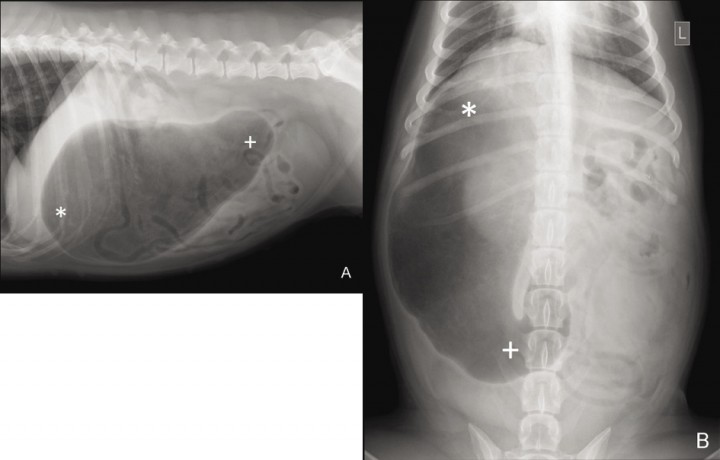

La radiografía es de utilidad para confirmar y diferenciar la dilatación gástrica de la DVG. Antes de realizar el examen radiográfico se debe descomprimir el abdomen por medio de un trocar o una sonda orogástrica.[ Monnet E. Gastric dilatation-volvulus syndrome in dogs. Vet Clin Small Anim Pract 2003; 33: 987-1005. [PubMed] , Cornell K. Gastric dilatation and volvulus. En Tobias KM, Johnston SA (ed): Veterinary Surgery Small Animal. Vol. 2. St. Louis, Missouri, Elsevier Saunders, 2012; 1508-1510. ] La radiografía debe realizarse en decúbito lateral derecho. Cuando el vólvulo se produce por la rotación sobre el eje transversal del estómago, se observa una imagen de bicompartimentación debido a la acumulación de aire en el píloro y el fundus (Fig. 5).[ Monnet E. Gastric dilatation-volvulus syndrome in dogs. Vet Clin Small Anim Pract 2003; 33: 987-1005. [PubMed] , Cornell K. Gastric dilatation and volvulus. En Tobias KM, Johnston SA (ed): Veterinary Surgery Small Animal. Vol. 2. St. Louis, Missouri, Elsevier Saunders, 2012; 1508-1510. ] Cuando la DVG es debida al giro sobre el eje longitudinal, se puede visualizar el estómago desplazado caudalmente y el fundus localizado en el lado derecho (Fig. 6).[ Carrillo JD, Escobar M, Soler M, Agut A. ¿Cuál es tu diagnóstico?. Clin Vet Peq Anim 2015; 35: 123-125. ]

<p>Radiografía lateral derecha de la cavidad abdominal craneal en un perro con DVG donde puede visualizarse una gran distensión gástrica y el signo de bicompartimentación, indicativo de vólvulo gástrico sobre el eje transversal, observándose el antro pilórico dorsalmente (x) y el fundus ventral (*).</p>

Radiografía lateral derecha de la cavidad abdominal craneal en un perro con DVG donde puede visualizarse una gran distensión gástrica y el signo de bicompartimentación, indicativo de vólvulo gástrico sobre el eje transversal, observándose el antro pilórico dorsalmente (x) y el fundus ventral (*).

<p>Radiografía lateral derecha (A) y dorso-ventral (B) de la cavidad abdominal tras la descompresión, en un perro con DVG por rotación sobre el eje longitudinal, donde puede visualizarse la lateralización del fundus (*) hacia la derecha y el desplazamiento caudal del antro pilórico (+). (Copyright de AVEPA, utilizado con autorización).</p>

Radiografía lateral derecha (A) y dorso-ventral (B) de la cavidad abdominal tras la descompresión, en un perro con DVG por rotación sobre el eje longitudinal, donde puede visualizarse la lateralización del fundus (*) hacia la derecha y el desplazamiento caudal del antro pilórico (+). (Copyright de AVEPA, utilizado con autorización).